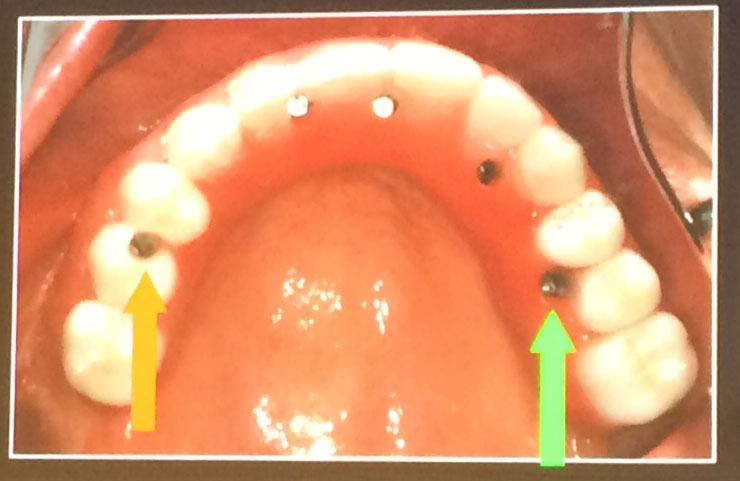

The zygoma dental implant treatment is done in one phase:

• Tooth extraction, if needed

• Implant placement

• Placement of the fixed prosthesis to implants

After surgery, patients leave with a temporary prosthesis. After a suitable amount of healing time, the patient will be able to come in for a“Teeth in a Day” procedure.